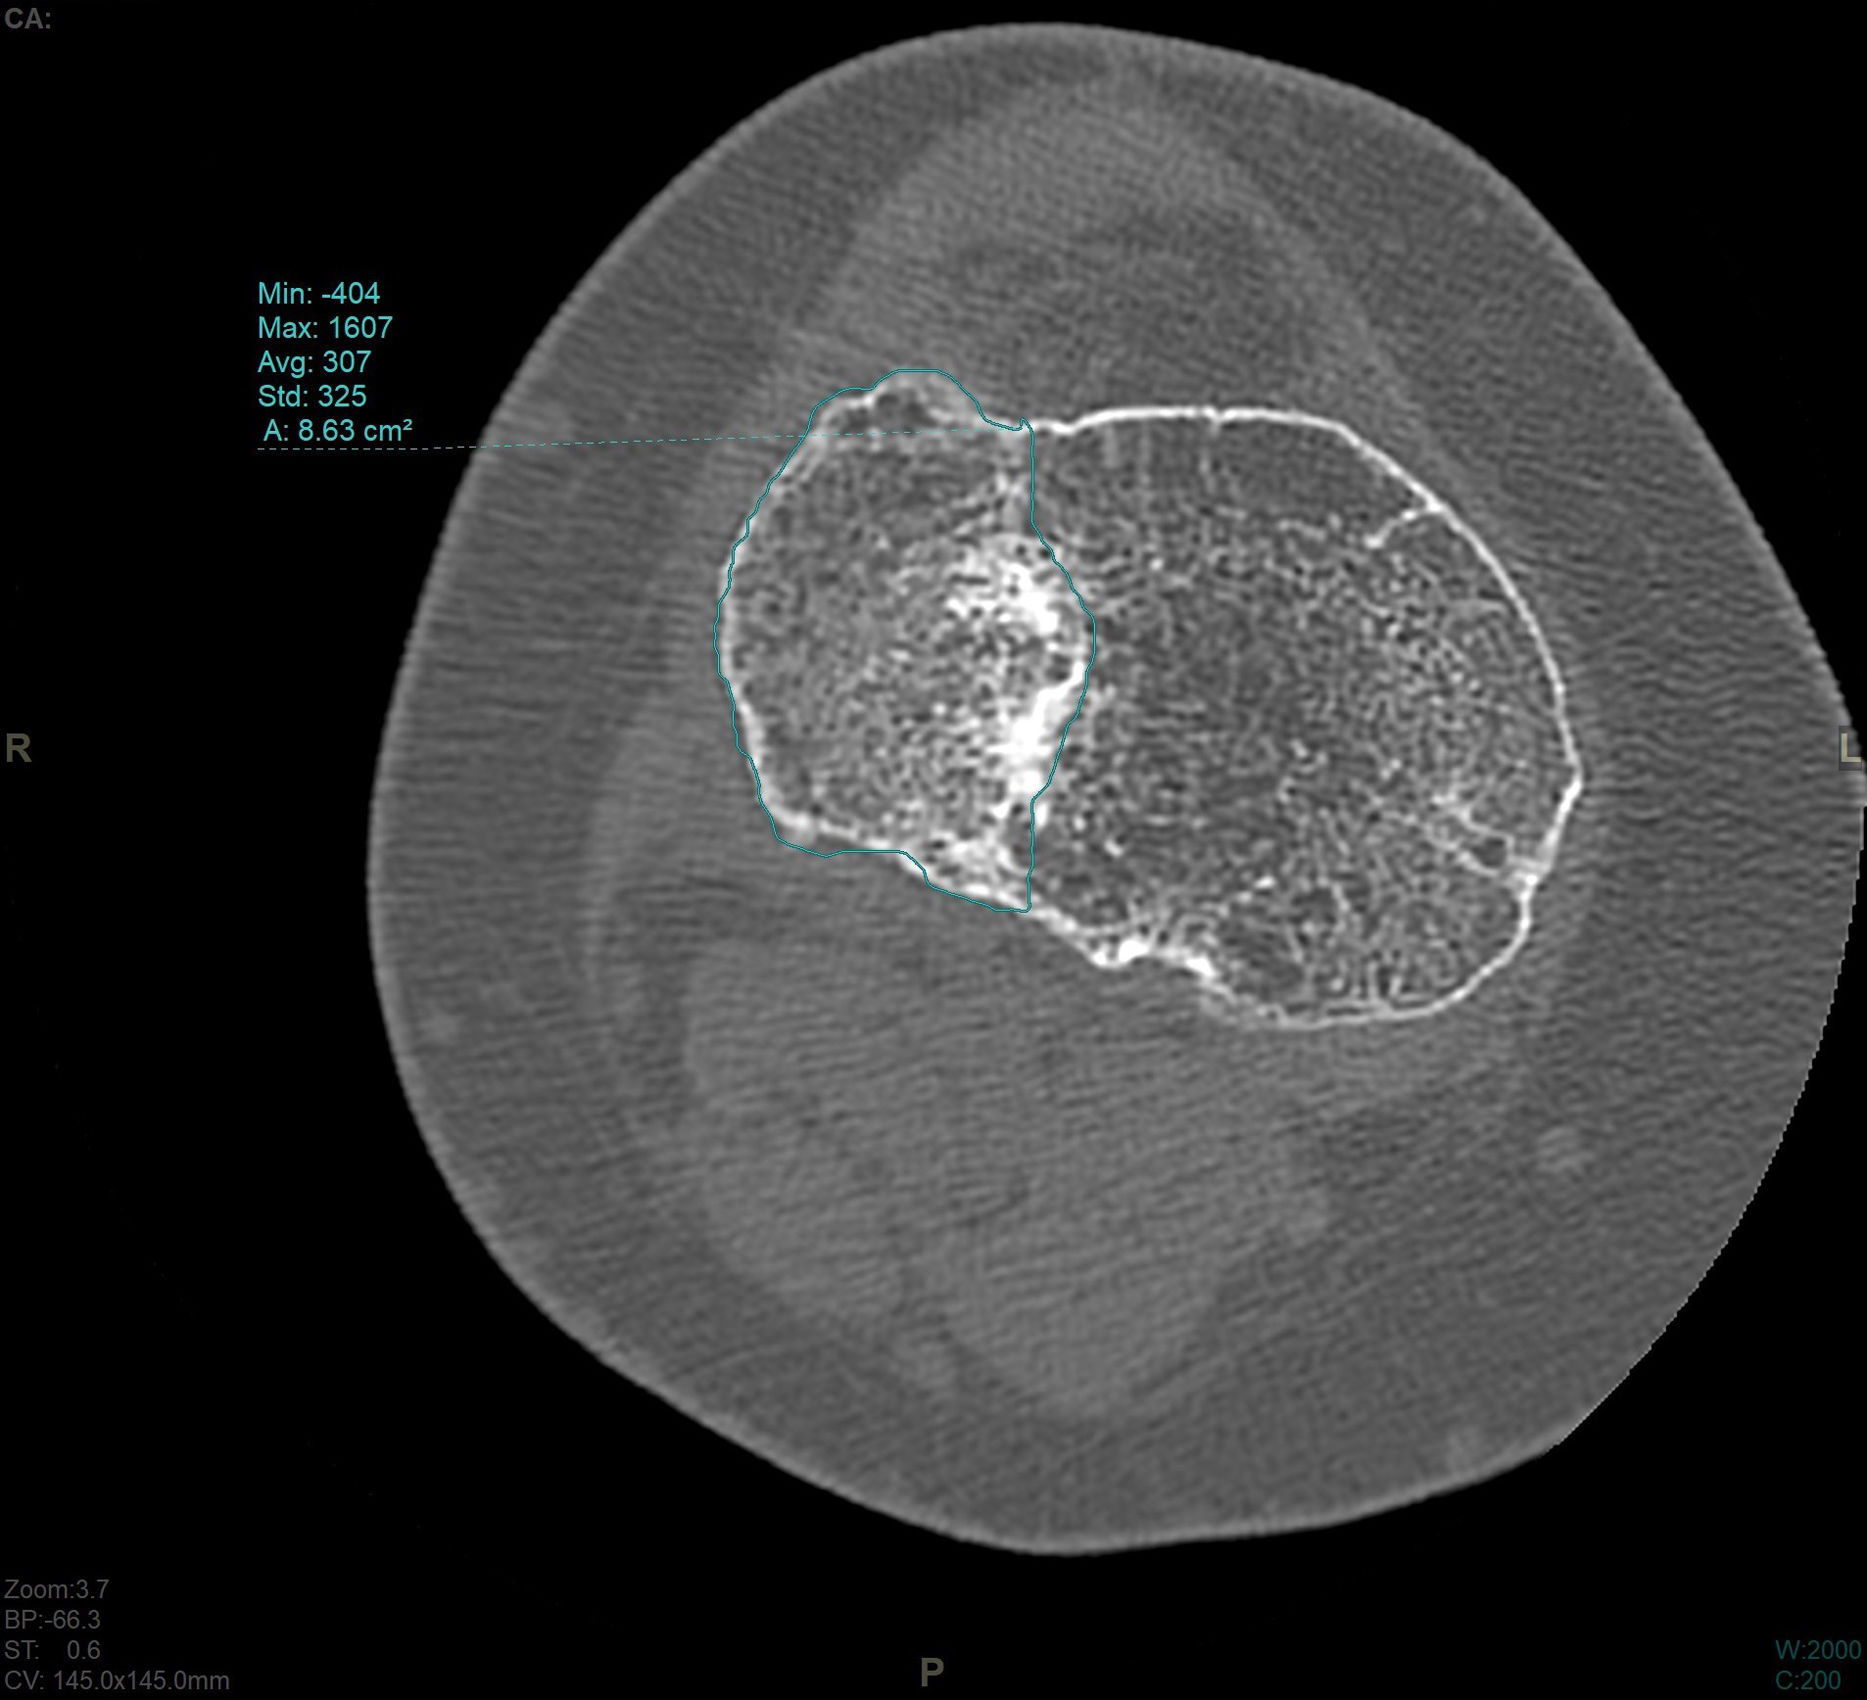

En el estudio de TC se hizo una adquisición volumétrica en un equipo multicorte a 0,6mm con posteriores reconstrucciones multiplanares de 1,5mm de espesor y 1,0mm de intervalo. En la reconstrucción en el plano coronal se analizó el punto de mayor depresión de la fractura en mm que se corresponde con el escalón articular máximo y la anchura máxima/diámetro transversal en mm; en el plano sagital se midió el diámetro máximo anteroposterior en mm del escalón articular y la caída máxima (slope) de la meseta tibial externa en grados (fig. 3). En el post-procesado en el plano axial se delimitó el contorno de la fractura y se calculó el área afecta en cm2, así como el diámetro mayor anteroposterior y la anchura máxima en mm (diámetros máximos anteroposterior y transversal) (fig. 4).

El escalón medio medido en TC fue de 3,6mm (DE: 1,9mm). El área media medida en TC fue de 17,57cm2 (DE: 6,1cm2) El slope medio fue 12,3grados (DE: 5,3grados).

| Área (cm2) | 17,57 | 6,1 | 15,16 | 19,99 | 6,32 | 32,43 |